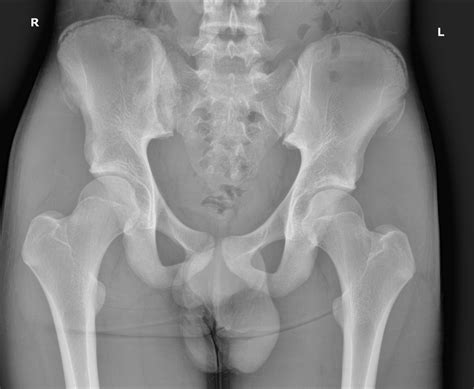

If you suspect an avulsion injury, professional medical diagnosis is vital. Doctors typically use physical examinations and imaging techniques to confirm the diagnosis. An X-ray is usually the first line of defense to visualize the bone fragment. In more complex scenarios, an MRI or CT scan might be ordered to evaluate the extent of soft tissue damage and the exact displacement of the bone.

Common sites for these fractures include:

• Ischial Tuberosity: Where the hamstring muscles attach (often during sprinting).

• Anterior Inferior Iliac Spine (AIIS): Where the rectus femoris (part of the quadriceps) attaches (often during kicking or jumping).

• Anterior Superior Iliac Spine (ASIS): Where the sartorius muscle attaches.

• Iliac Crest: Where the abdominal muscles attach.